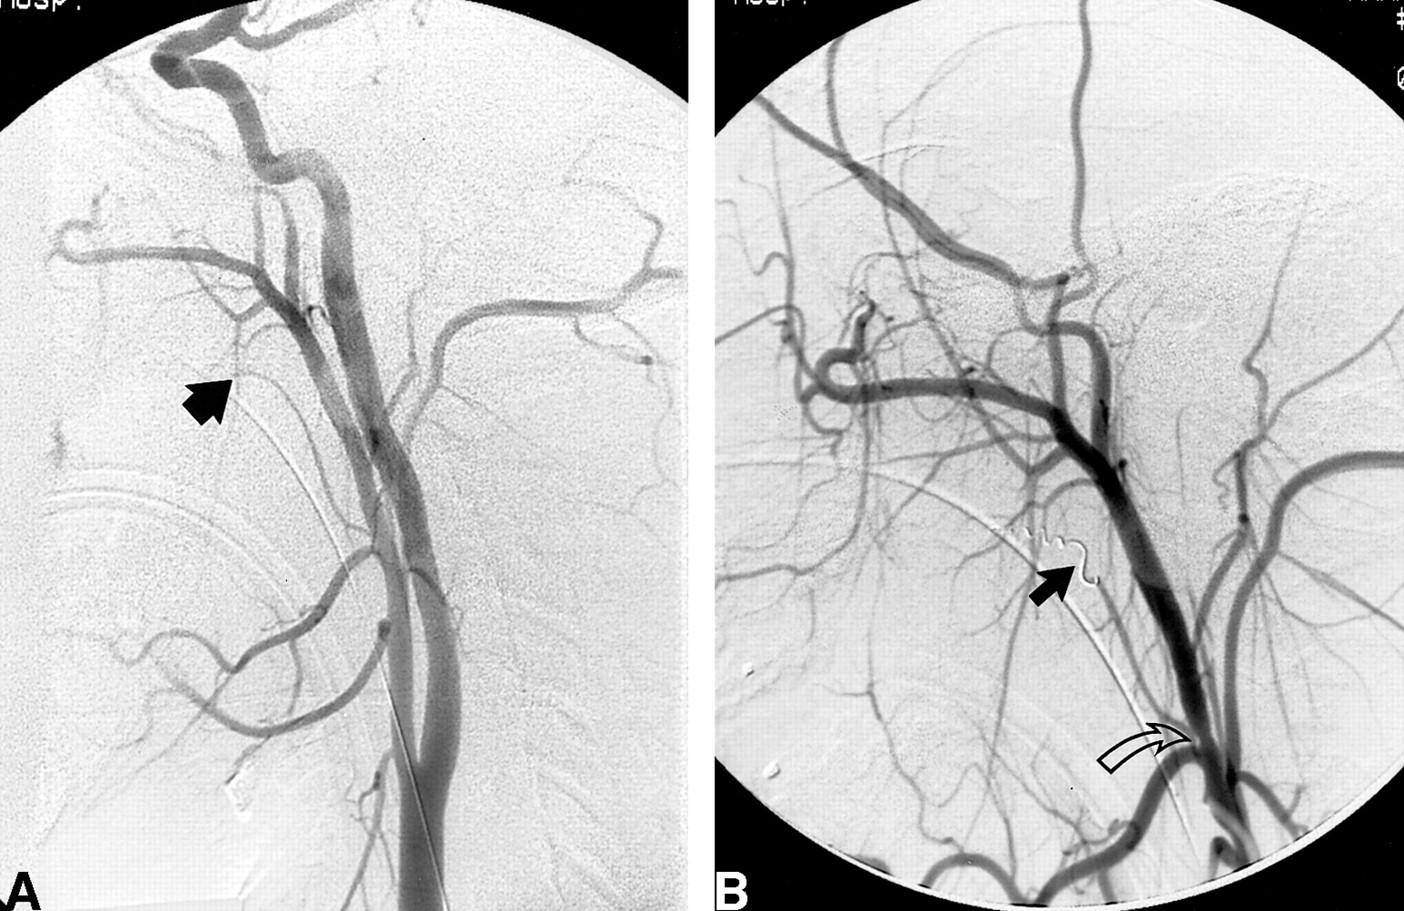

Case 2: 5-year-old girl with PTAH.

A, An ECA angiogram shows proximal irregularity of the lingual artery (arrow). A subsequent selective lingual artery injection showed free extravasation of contrast material from this point, confirming the source of PTAH.

B, Coil embolization of the proximal lingual artery (solid arrow). A portion of the distal lingual artery is reconstituted via generous collateral ECA branches (open arrow). This situation is commonly encountered in the ECA territory and can contribute to rebleeding, which may be minimized by embolization distal and proximal to the site of injury.

Upon arrival in the emergency department, she was hemodynamically stable. Given her clinical course, angiographic assessment was deemed prudent, particularly given a further reduction in her hematocrit to 29.2. Under general anesthesia, the right common femoral artery was punctured and a 5F sheath was placed. The left ECA was selected and injected with contrast material, revealing irregularities of the proximal lingual artery (Fig 2A). The ascending pharyngeal artery was selected first and polyvinyl alcohol (PVA) particles measuring 150 to 250 μm were injected. In addition, a 3- × 7-mm platinum coil was deployed in the ascending pharyngeal artery. The lingual artery was then selected and injected. Free extravasation of contrast material was noted in the surrounding extraluminal space. Multiple 3- × 7-mm platinum coils were deployed as well as three 0.2- × 8.0-cm Guglielmi detachable coils. As the catheter was retracted, the origin of the lingual artery was closed using three 3- × 7-mm platinum coils, and occlusion of the vessel was confirmed angiographically (Fig 2B). After embolization, the patient remained stable and tolerated a full oral diet. She was discharged 2 days after embolization, and no subsequent bleeding episodes were reported.

Our embolization procedures are typically performed with a 0.010- or 0.018-inch microcatheter via a 5F or 6F sheath placed within a common femoral artery. In medium to large vessels, the site of injury is isolated or trapped by both distally and proximally situated coils. This serves to diminish the likelihood of subsequent collateralization and rebleeding, a distinctly common occurrence in the ECA vascular territory (Fig 2B). In smaller injured branch end-vessels, distally placed gelatin sponges or coils are generally sufficient to achieve complete embolization, since the risk of collateralization and rebleeding is significantly reduced.